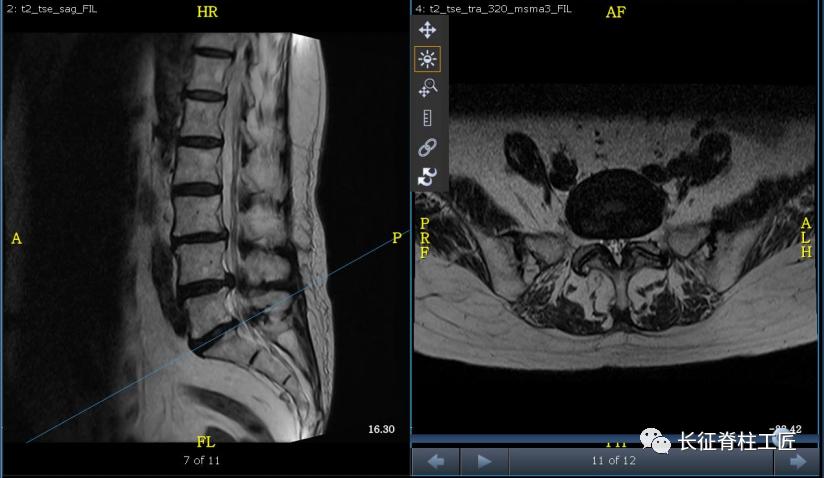

入院检查,腰部疼痛,后伸时加剧,局部压痛,双下肢肌力减退。X线检查,L4、L5骨质增生,MRI显示L4/L5、L5/S1椎间盘突出,马尾神经受压明显,被确诊为腰椎管狭窄症。

脊柱外科史国栋主任带领团队详细讨论,决定行椎管减压植骨融合内固定术。秉持微创的理念,术中通过精确的切口设计、肌肉组织的保护、手术时间的控制、后侧韧带复合体的保留等措施,在开放的手术中微创的完成了手术。